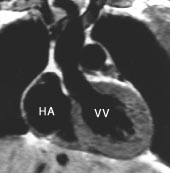

T1-vektede MR-bilder viser det normale perikard som en mørk stripe mellom to lyse vev, det epikardiale fettvev og det perikardiale fettvev (fig 8, 9). Fortykkelse av perikard ( ≥ 4 mm) kan av og til sees ved akutt perikarditt, men er mer vanlig ved kronisk perikarditt. MR er en sensitiv metode til å påvise konstriktiv perikarditt (20). I tillegg til perikardfortykkelsen, sees dilatasjon av høyre atrium, v. cava inferior og levervenene og normalt stor eller liten høyre ventrikkel. MR er imidlertid en dårlig metode til å påvise forkalkninger i perikard. Perikardvæske har et varierende utseende ved MR avhengig av innhold av protein og andre makromolekyler. Stormolekylære stoffer forkorter væskens T1 og forårsaker økt signalstyrke på T1-vektede bilder. Eksudatet i perikard ved den sterkt inflammatoriske uremiske perikarditt gir således et moderat kraftig signal på T1-vektede bilder, mens det perikardiale transsudat som sees ved f.eks. hjertesvikt, har nesten manglende signal på T1-vektede bilder (fig 7). Hemoperikardium har et karakteristisk utseende med en intens signalstyrke på T1-vektede bilder.